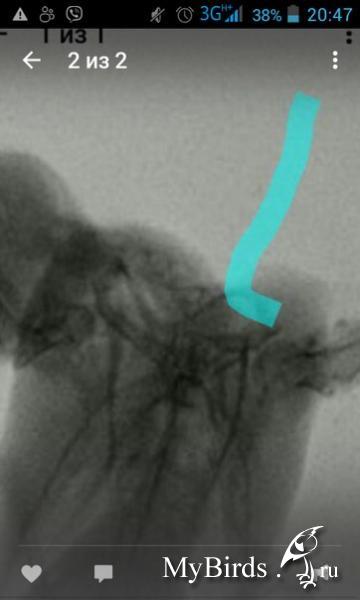

Сделали ренген, два ветврача ни чего не увидели(

загадочная поза для рентгена) если проблемы с вилкой, так не увидеть, например.

мне не нравится положение левого плеча, это может быть сустав. но на рентгене вопрос есть скорее к правому, а на видео левое крыло может быть так неудобно расположено потому что вы все время вертите рукой.

в целом - курс реабилитации так и так не завершен. по поводу того же чмт надо бы продолжить. траумель желательно тоже попить. хорошо прощупать суставы, написать есть ли на ощупь сейчас какая-то разница слева и справа - плечевые особенно? ну, по поводу вилки - только нормальный рентген на спине может показать.